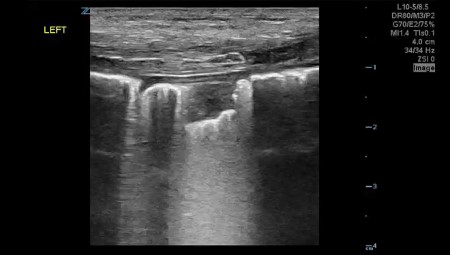

El derrame pleural se observa como un líquido anecogénico (figura 5) que se mueve libremente con los cambios de posición y respiración del paciente.

Si el derrame es muy significativo puede llegar a haber una pérdida del signo de la cortina (durante cada inspiración los artefactos originados por el pulmón aireado impiden identificar el diafragma y órganos abdominales) (figura 6), el que se observa en el seno costo-diafragmático cuando existe ausencia de derrame.

En el derrame pleural además podremos encontrar el signo de la espina (figura 7): consiste en la visualización de los cuerpos vertebrales en la cavidad torácica (entonces, evidentemente, sobre el diafragma). Generalmente no se ven, salvo que haya presencia de fluido en dicha zona (el líquido transmite las ondas de ultrasonido mucho mejor que el aire).

Otros signos que se pueden observar son el signo del cuadrilátero (o signo del cuadrado), que consiste en una colección limitada por sombra de costillas, pleura parietal y pleura visceral, formando un cuadrilátero; y el signo del sinusoide, que se explora en el modo M y consiste en un movimiento en dirección al transductor de la línea que representa la interfaz, generalmente la pleura visceral, con la inspiración. El parénquima pulmonar se dirige hacia la línea de la pleura parietal con cada inspiración. Indica baja viscosidad del derrame, pudiendo estar ausente si hay septos o es muy viscoso (figura 8).

Resumen de síndrome de derrame pleural: Contenido libre anecogénico, ausencia del signo de la cortina, presencia del signo de la espina, presencia del signo del cuadrilátero, presencia del signo del sinusoide.